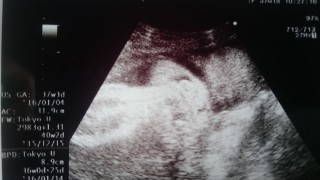

写真:37w0d:ぴよちさん:2,590g

2人目の出産で2,590gとの事です。上の子は2,880gで出産。2人目も同じくらいで生まれるかもねーと言われました!女の子でぷくぷくしてきました!いつ会えるのかドキドキ…楽しみです!